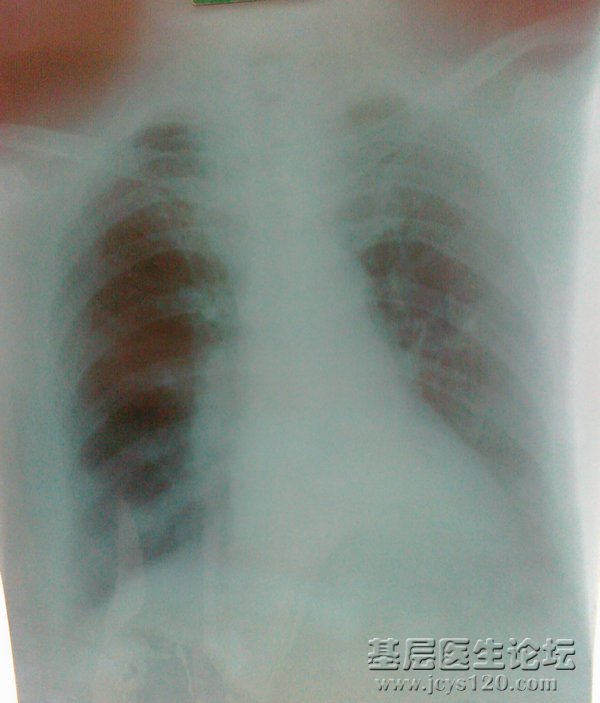

• 肺结核还是肿瘤? attach_img agree

• sxmz 2012-6-11

• 2、女性,65岁,哮喘、肺气肿病史十余年,因发热、咳嗽、咳痰一周入院,昨天在医院检查WBC22.3×10 9 白蛋白低于正常值,总胆红素稍高(具体数值稍后补上) 肝脏超声检查:肝硬化并内见多个低回声结节,少量腹水。 ...  阅读全文>